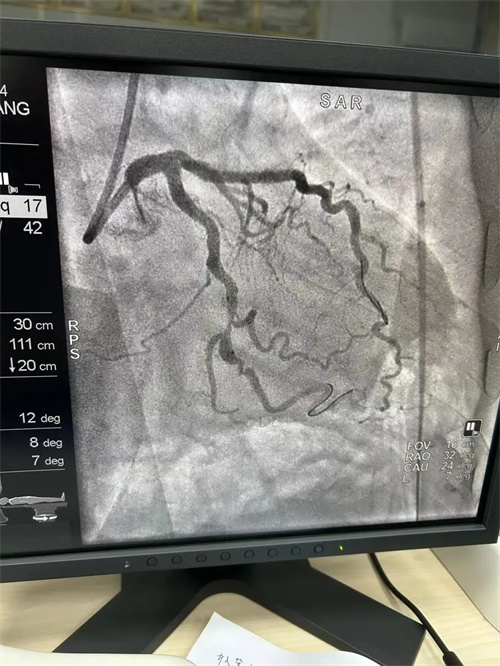

患者李大爷(化名),70岁,近半月来频繁出现胸痛、胸闷等症状,严重影响了日常生活。经过冠状动脉造影检查,李大爷被诊断为冠状动脉粥样硬化性心脏病,前降支、回旋支均达95%狭窄,需进行冠状动脉支架植入手术。经过充分的术前准备,犍为县中医医院介入诊疗中心医护团队为李大爷实施了手术。手术过程非常顺利,分别于前降支、回旋支各安置支架1枚,术后李大爷的胸痛、胸闷症状明显缓解。

![]() |

支架前